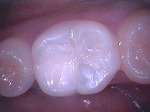

◆ドックベストセメント療法

削らないむし歯治療で注目されているセメントです。

セメントの殺菌効果により、通常のでは神経を抜くであろう深いむし歯治療においても有効です。

ドックスベストセメントを使用することで歯の神経保存率が高まります。

この治療は自費治療となります。

ドックスベストセメント

~初診~

~歯髄に近い深い虫歯~

~ドックベストセメント処置~

~グラスアイオノマー仮封~

~CR充填~